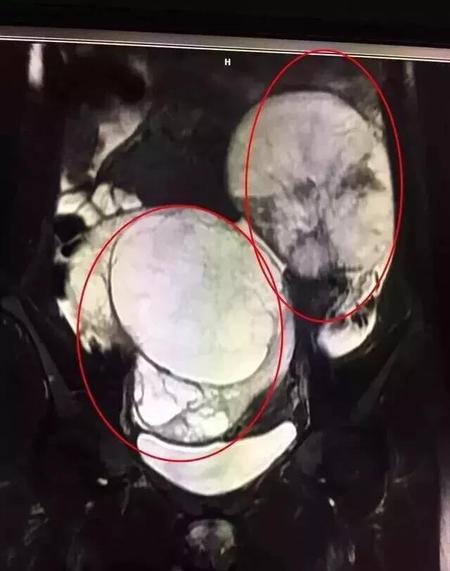

还见过一个32岁,停经2个月,腹部逐渐隆起就诊,都以为是怀孕了。做了超声发现,不是怀孕,而是双侧卵巢各长了1个10cm大的肿瘤,一共20cm大的肿块在肚子里,跟怀孕的症状一样,让人错以为怀孕了。下图。

随后做了全腹部的CT发现胃壁也明显增厚。有经验的医生看到胃有问题,双侧卵巢也有问题的话,一定要想到是胃癌转移到双侧卵巢的可能,影像科给出准确的诊断,可以让患者和临床医生少走很多弯路。